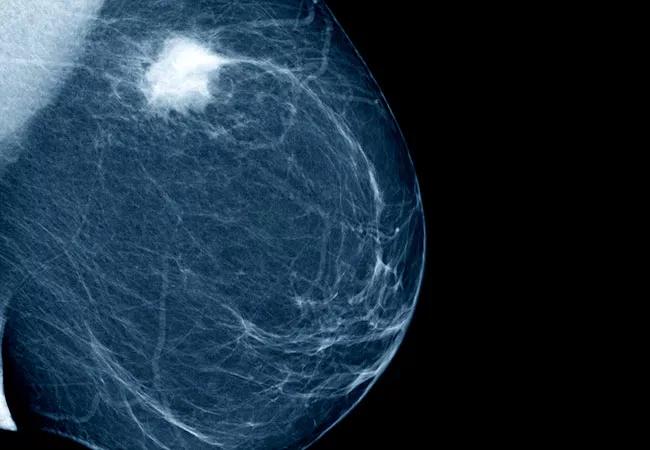

More than 70% of breast cancer patients have estrogen-receptor-positive (ER+) tumors. Antiestrogen therapy plays a major role in their treatment. However, most advanced-stage and some early-stage breast cancer patients will develop resistance to endocrine therapy.

What causes ER+ breast cancer cells to grow despite antiestrogen therapy? One answer is the PI3K signaling pathway. About 40% of hormone-receptor-positive (HR+) breast cancers have a PIK3CA mutation, which sends the PI3K pathway into overdrive, speeding cell replication.